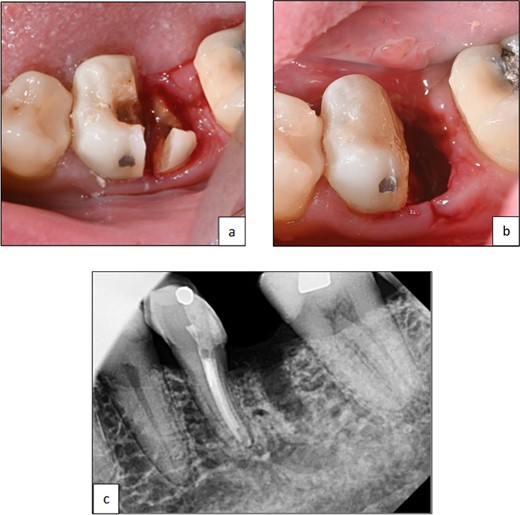

Following root canal treatment, hemisection and removal of the distal root were performed under local anesthesia. The furcation area was marked on the crown to guide tooth sectioning. Using a low-speed surgical fissure bur under normal saline irrigation, a vertical cut was made to separate the tooth. The distal root was elevated and removed in one piece using a periosteal elevator. Sharp edges and margins were smoothened, and the coronal tooth structure was restored. Hemostasis was achieved using a pressure pack.

The patient was monitored for one year with no reported symptoms. Due to extensive filling and secondary caries in the adjacent left second mandibular molar (tooth 37), both the mesial root of tooth 36 and tooth 37 were prepared for a zirconia bridge. Tooth 36 received a full-coverage crown, while tooth 37 was restored with an onlay. Tooth 36 was anatomically restored to conform esthetically and functionally with the existing occlusion (Fig. 4 and 5).

Clinical photographs showing (a) line of resection through furcation area and separation of mesial and distal roots, (b) after elevation of root and smoothening of sharp edges, (c) periapical radiograph of tooth 36 after hemisection and removal of distal root.

Clinical photographs showing (a) zirconia bridge design, (b) final prosthesis after cementation, (c) periapical radiograph post-cementation of zirconia, the bridge shows a good adaptation of the restorative margins.